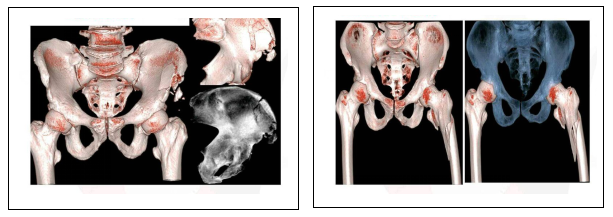

三.骨科系统:

可以沿任意轴观察骨骼,任意角度重建可以发现隐匿的骨折、复杂多发骨折、骨折手术效果评估。

左髂骨翼骨折 左股骨转子间骨折